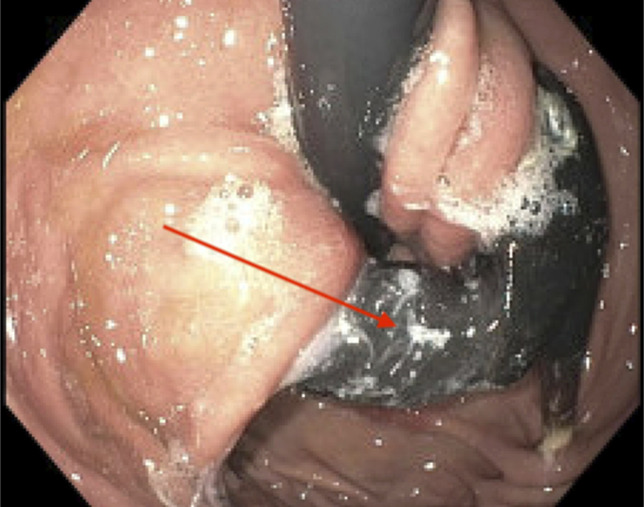

A woman in her 60s presented with epigastric pain and fever, initially managed as acute cholecystitis. Imaging was inconclusive, but esophagogastroduodenoscopy on hospital day 4 revealed gastric band erosion 20 years postlaparoscopic adjustable gastric banding. Surgery confirmed partial erosion with abscess along the band tract and subcutaneous port site. Postoperative complications included gastric leak, candida infection, and abdominal wall abscess, managed with antibiotics, drainage, and supportive care. She was later discharged on oral antibiotics but developed a pulmonary embolism requiring anticoagulation. Laparoscopic adjustable gastric banding complications, including erosion, should be considered even decades later; early endoscopy may prevent delays and related complications.